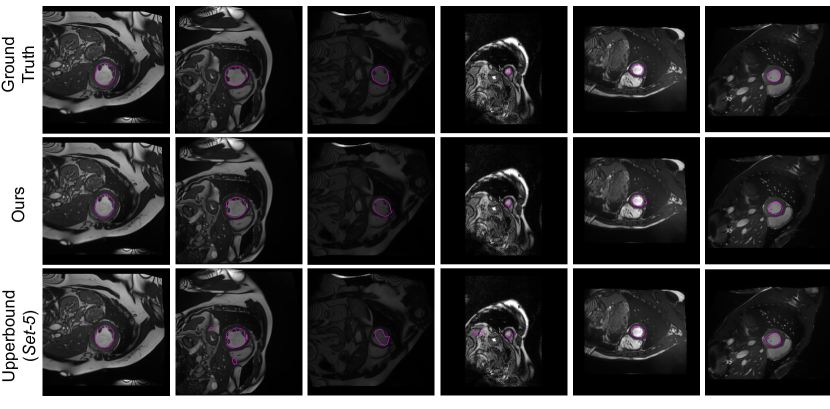

Figure 9: Probability maps obtained by the proposed KL𝐾𝐿KL and KL+Ent𝐾𝐿𝐸𝑛𝑡KL+Ent models.

In addition to the numerical results presented before, we also depict qualitative results in Fig. 8 and Fig. 9. Particularly, Fig. 8 depicts the segmentation results for the models evaluated in Table 1. We see that results obtained by models with a single network typically under-segment the object of interest (first row) or generate many false positives (second row). Decoupling the decoding branches might reduce the false positive rate, however, it also tends to under-segment the target. Finally, we observe that both of our formulations achieve qualitatively better segmentation results, with the KL+Ent model yielding segmentations similar to those generated by the upper bound model. Furthermore, in Fig. 9, we illustrate additional qualitative results of our models. We observe that without the entropy term our model produces less confident predictions, which results in more noisy segmentations.

Qualitative evaluation is visually assessed in Fig. 10, which depicts the segmentation results across models on the Set-3 and Set-5 settings. Similarly to the visual examples in Fig. 8, single models generate inconsistent segmentations, which result in both large under and over-segmentations. Even though decoupling single models in dual-stream architectures seem to reduce the amount of false positives, it typically comes at the price of failing to identify target regions. In contrast, both of our models provide a substantial improvement on the segmentation quality, with the model integrating the KL and the entropy terms providing the closest results to the ground-truth.